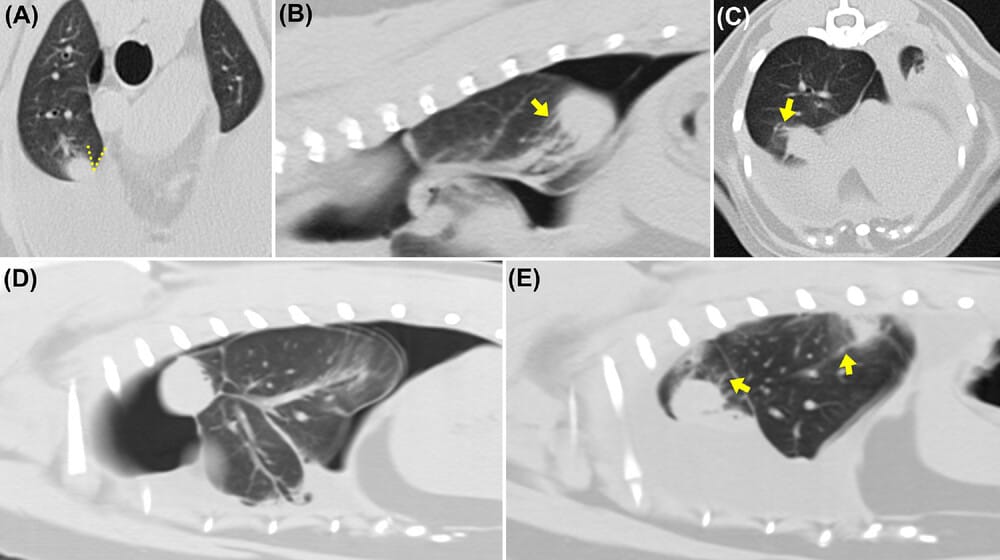

Pre-contrast thoracic CT transverse (A, C) and multiplanar reconstructions (MPR) parasagittal (B, D, E) images in a lung algorithm in dogs (A, C) and cats (B, D, E) diagnosed with chylothorax and restrictive pleuritis. Perilesional tortuous bronchi and vessels coalescing to the pulmonary nodular lesions (comet tail signs) are present (yellow arrows on images B, C, E). The pulmonary nodular lesions additionally create an acute angle with the abutting visceral pleura, depicted by the discontinuous yellow lines on image A. Rounding of the lung margins and a moderate pneumothorax (B, D) can also be identified